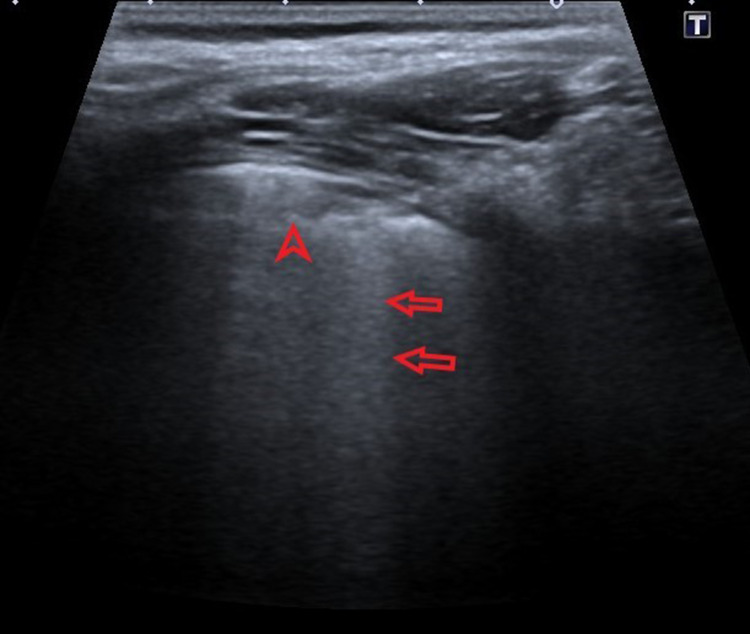

Picture 2.

Ultrasound profile 2, presence of B-lines, hyperechoic vertical lines (pointed red arrows)

Picture 3.

Ultrasound profile 2, confluent B lines (red arrows) with subpleural consolidation (pointed red arrow)

(a) B-lines which represent an accumulation of fluid into interstitial and alveolar space. B lines are hyperechoic vertical lines, positioned perpendicular to A-lines, erase them, and distributed from the pleural line to the bottom of the screen.

(b) Subpleural consolidation which can be seen as isoechoic to hypoechoic areas of the lung parenchyma, with irregular shape (round or triangular), predominantly found in subpleural space and posterior parts of the lungs.